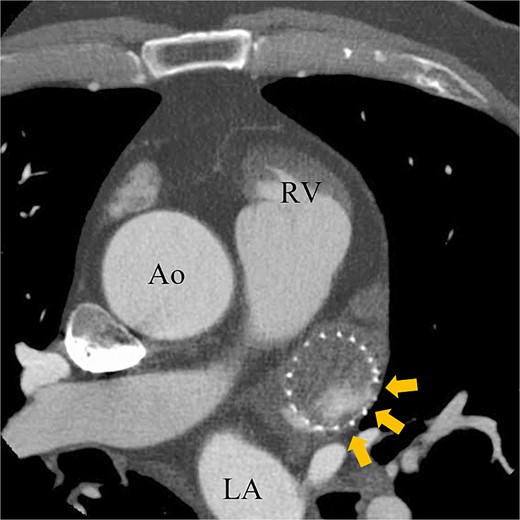

A 74-year-old male with a history of chronic atrial fibrillation (AF) for over 10 years, cardioembolic stroke, and cerebral hemorrhage, who had undergone LAA closure using the WATCHMAN device 1 year prior, was admitted after a follow-up contrast-enhanced CT scan revealed a 25-mm intracardiac mass in the right atrium (RA) (Fig. 1). After the WATCHMAN implantation, the patient was initially on direct oral anticoagulant (DOAC) but switched to dual antiplatelet therapy (DAPT) following the placement of a drug-eluting stent during percutaneous coronary intervention performed 9 months later. Transthoracic echocardiography revealed a left ventricular ejection fraction of 61% and a right atrial mass measuring 17 × 19 mm with slight mobility (Fig. 2). Despite anticoagulation therapy with heparin, the right atrial mass did not reduce in size. The patient decided to undertake surgical removal of the mass due to the potential risks of tumor or embolization. Additionally, contrast-enhanced CT showed a peri-device leak around the WATCHMAN device (Fig. 3). Considering the patient’s history of cerebral hemorrhage and the anticipated future cessation of anticoagulation therapy, we determined to perform WATCHMAN device explantation and LAA closure. Preoperative contrast-enhanced CT showed no thrombi attached to the WATCHMAN device and sufficient distance from the left circumflex artery (LCX) and the device (Fig. 4). We planned to remove the device by incising from the outside surface of the LAA. The Maze procedure was not performed because it was considered less effective due to the patient’s history of AF lasting more than 20 years and the presence of flat f-waves in lead V1 on the 12-lead electrocardiogram.

Preoperative enhanced computed tomography imaging showing a 25-mm intra-cardiac mass in the RA (arrows). RV, right ventricle; LA, left atrium; LV, left ventricle.